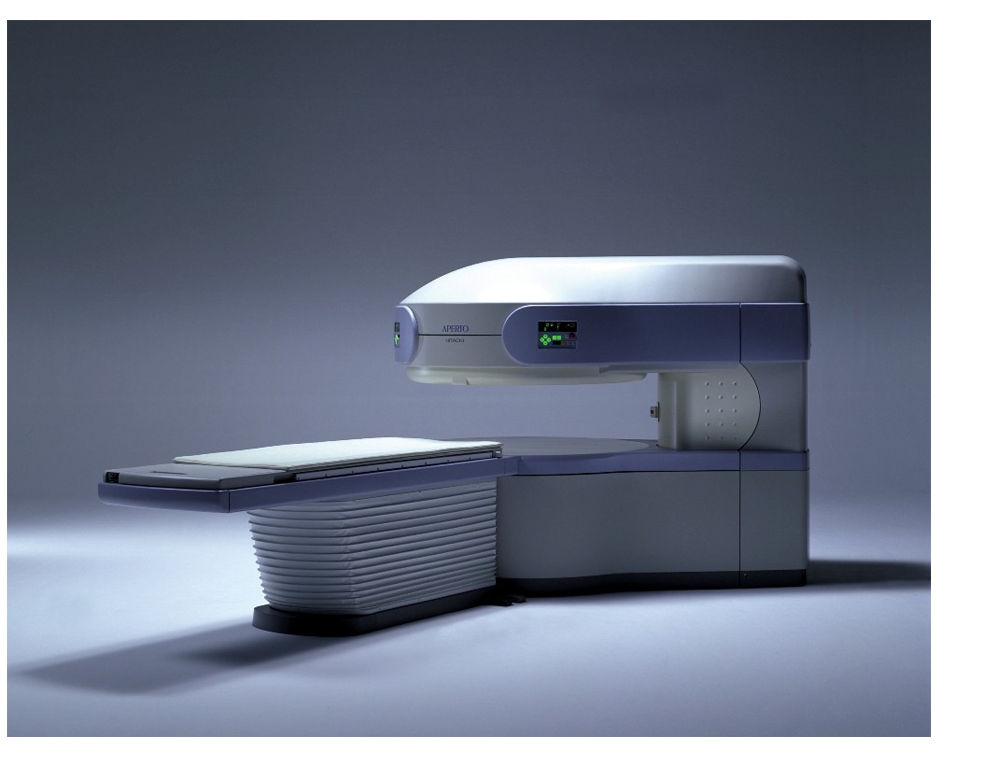

La RM es un examen de diagnóstico seguro, preciso y no invasivo que permite detectar y diagnosticar enfermedades. Funciona mediante la emisión de ondas de radiofrecuencias desde las diferentes partes del cuerpo, después de ser expuestas a un poderoso campo magnético.

La RM aporta importantes contribuciones diagnósticas, que la sitúan como método de primera elección en procesos que afectan al sistema nervioso central y en toda la patología del sistema músculo-esquelético.

La Resonancia magnética es un examen de diagnóstico seguro, preciso y no invasivo que permite detectar

y diagnosticar enfermedades. Funciona mediante la emisión de ondas

de radiofrecuencias desde las diferentes partes del cuerpo,

después de ser expuestas a un poderoso campo magnético. Las

señales que se emiten se analizan y se traducen en imágenes de muy alta calidad. La Resonancia magnética es uno de

los mejores métodos para diferenciar las estructuras del cuerpo y

así poder detectar a tiempo alguna enfermedad y, debido a que no

usa radiación, es un procedimiento muy seguro.

La Resonancia Magnética (RM) es un método de

exploración cuya finalidad es la obtención de imágenes del interior

del cuerpo con el fin de evaluar su estado y forma a fin de

descartar patologías.